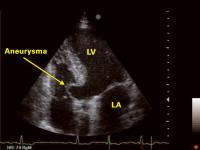

Interventrikuläres Septum - Aneurysma

Abbildung 1: Apikaler Vierkammerblick: Aneurysma des interventrikulären Septums; LA = linker Vorhof; LV = linker Vorhof